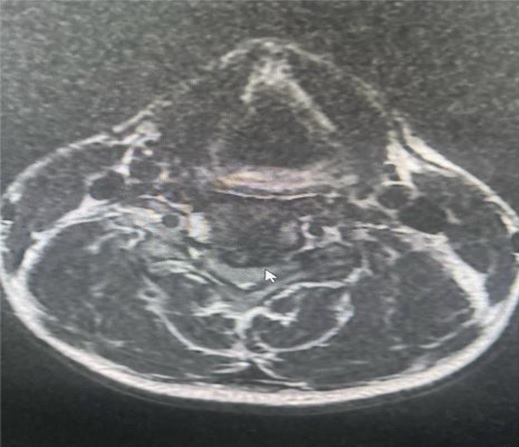

Qua thăm khám, các bác sĩ khoa Phẫu thuật Thần kinh Lồng ngực ghi nhận cơ lực hai tay giảm còn 4/5, kèm theo dấu hiệu chèn ép rễ thần kinh cổ. Hình ảnh cộng hưởng từ (MRI) cột sống cổ cho thấy khối thoát vị đĩa đệm cột sống cổ tầng C4–C5, khối thoát vị gây chèn ép thần kinh, phù hợp với biểu hiện lâm sàng của người bệnh.

Hình ảnh MRI thoát vị đĩa đệm C4-C5 chèn ép tủy sống trước mổ